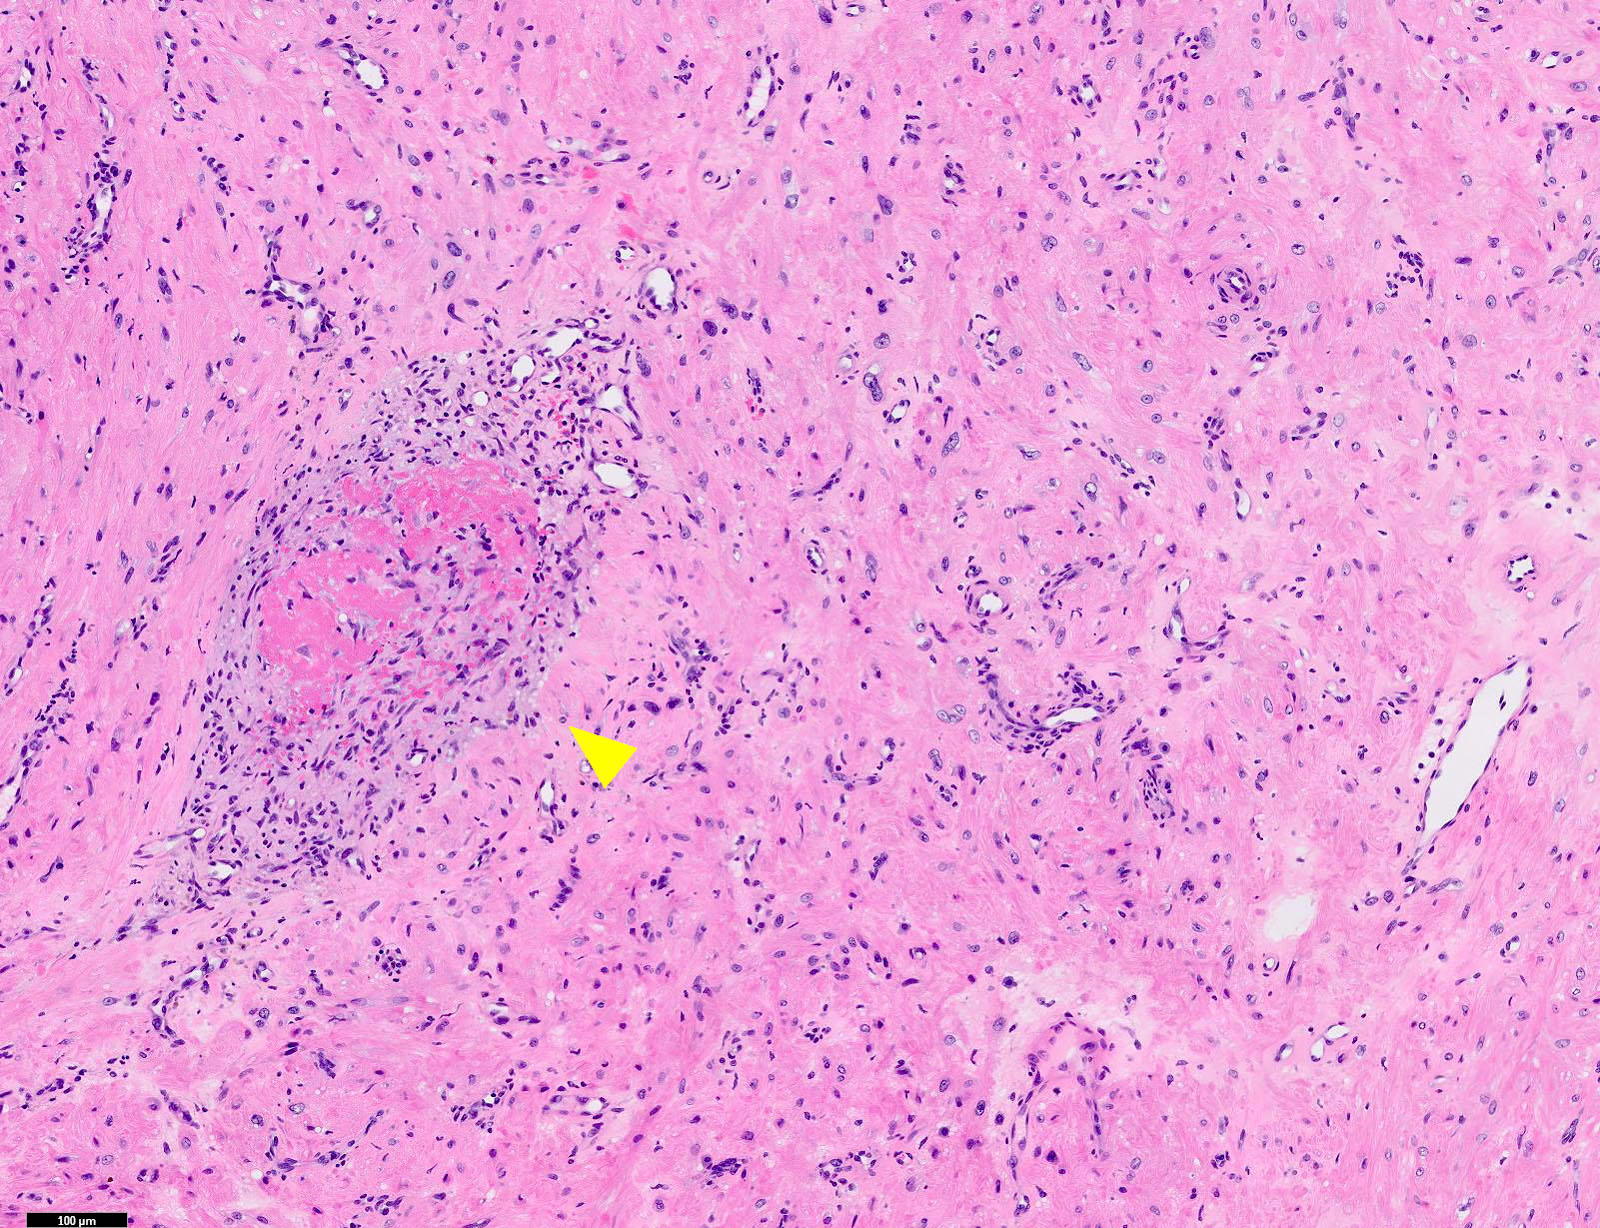

Microscopic (histologic) description

- Encapsulated proliferation of eosinophilic smooth muscle cells with minimal nuclear pleomorphism

- Rounded or slit-like veins with muscular walls present within the tumor (J Cutan Pathol 2017;44:342)

- Tumors can further be classified into 3 subcategories, first described by Morimoto et al:

- Cavernous type: dilated vascular channels, the walls of which are difficult to distinguish from the intervascular smooth muscle

- Venous type: thick walled vessels that are easily distinguished from the intervascular smooth muscle

- Calcification and marked degeneration, including hyalinization and myxoid changes, may be present (J Cutan Pathol 2017;44:342, J Ultrasound Med 2019;38:1201)

Microscopic (histologic) images

Contributed by Ohoud Aljarbou, M.D., Jijgee Munkhdelger, M.D., Ph.D. and Andrey Bychkov, M.D., Ph.D.

A. Angioleiomyoma. A mixture of smooth muscle bundles arranged in small fascicles and intervening vascular channels is noted. The concentric perivascular spindle cell proliferation which is characteristic for myopericytoma is absent. There are no glomus cells seen. Adipocytes are not seen in this image, which makes angiomyolipoma less likely.